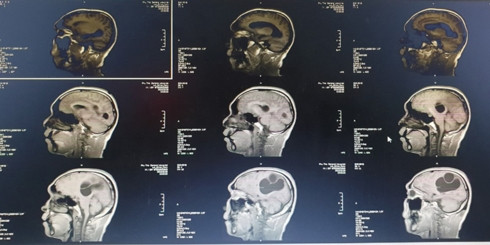

Bệnh nhân được chỉ định chụp Citi sọ não, kết quả cho thấy ổ sán não khổng lồ ở bán cầu trái và vùng thái dương đỉnh phải. Phù não đè đẩy đường giữa.